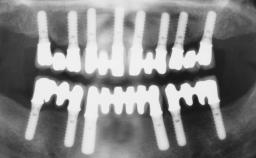

Conventional Loading of Eight Implants in the Maxilla and Final Restoration with a Full-Arch Gold-Ceramic FDP

# of Implants | 8 |

Type of Implants | One-Piece |

Loading Protocol | Conventional or early |